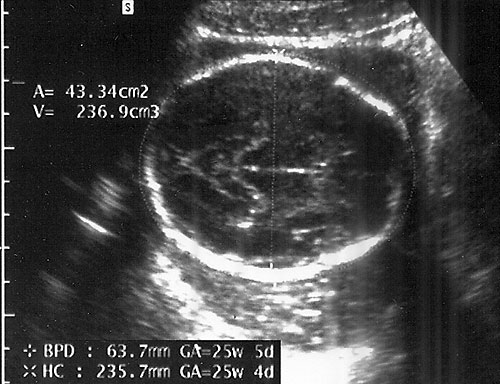

- Biparietal Diameter (BPD)/Head Circumference (HC)/Intracranial Anatomy — Ventricles/Atria/Posterior Fossa

- Accuracy is inversely related to gestational age: "one-two-three rule".

Measurements from outer edge at superior margin to inner margin at inferior margin to correct for fetal skull thickness (left). Proper measurement of head circumference (right). - Clinically meaningless, unless multiple parameters are measured and evaluated.

- Measuring BPD/HC

- Axial plane at level of septum cavum pellucidum and thalamic nuclei. (Shepard M, Filly RA. A standardized plane for bieparietal diameter measurement. J Ultrasound Med 1982;1(4):145-50.)

Normal BPD at level of thalami with cavum seen. - Falx: midline and perpendicular to angle of insonation. (Simpson GF, Filly RA. Comparison of fetal head circumference measurements using standard and long linear array transducers. J Diagn Med Sonogr 1988;4:2)